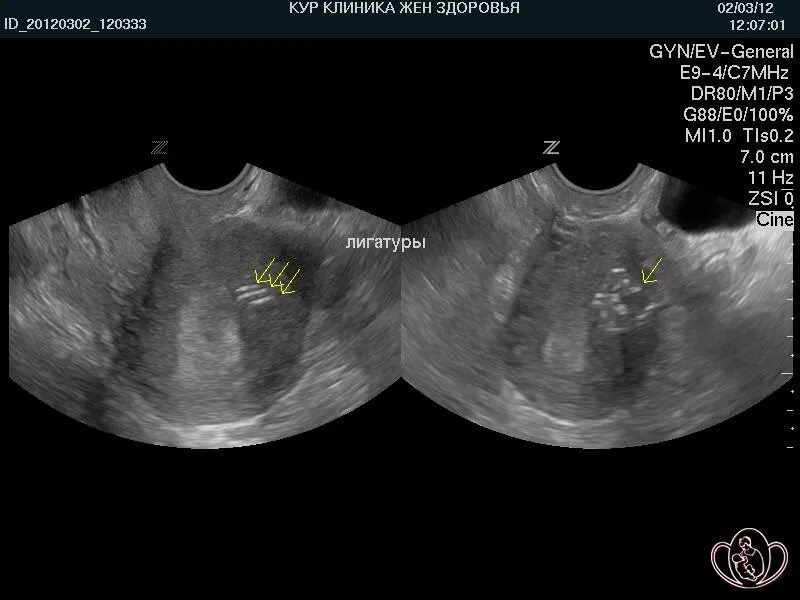

Можно ли забеременеть при загибе матки